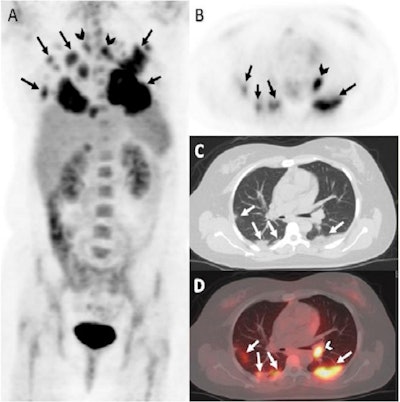

The researchers found 13 of 31 patients (41.9%) had positive PET/CT scans. Patients with positive scans had significantly higher rates of symptomatic COVID-19 infection (77% vs. 28%) and hospitalizations (46% vs. 0%) compared with patients with negative PET/CT scans.

Of the patients with positive scans, 11 out of 13 (84.6%) had FDG-avid lung findings, with mean lung SUVmax of 5.36; 6 of 13 patients (46.2%) had extrapulmonary findings of FDG-avid thoracic lymph nodes.